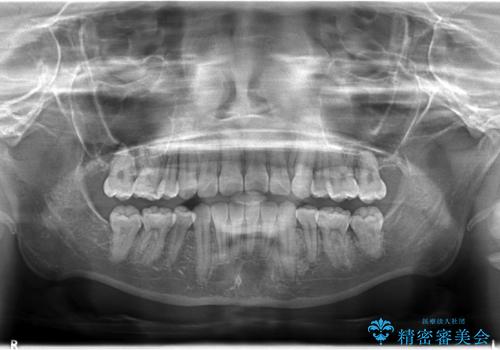

- 上下左右4本の小臼歯を抜歯、ラビアル・ワイヤー矯正を計画した。

抜歯をして第1小臼歯分のスペースを獲得することにより、ガタつきの改善と前歯のリトラクトをおこない、横顔の印象もすっきりとし、整ったEラインを作ることができました。